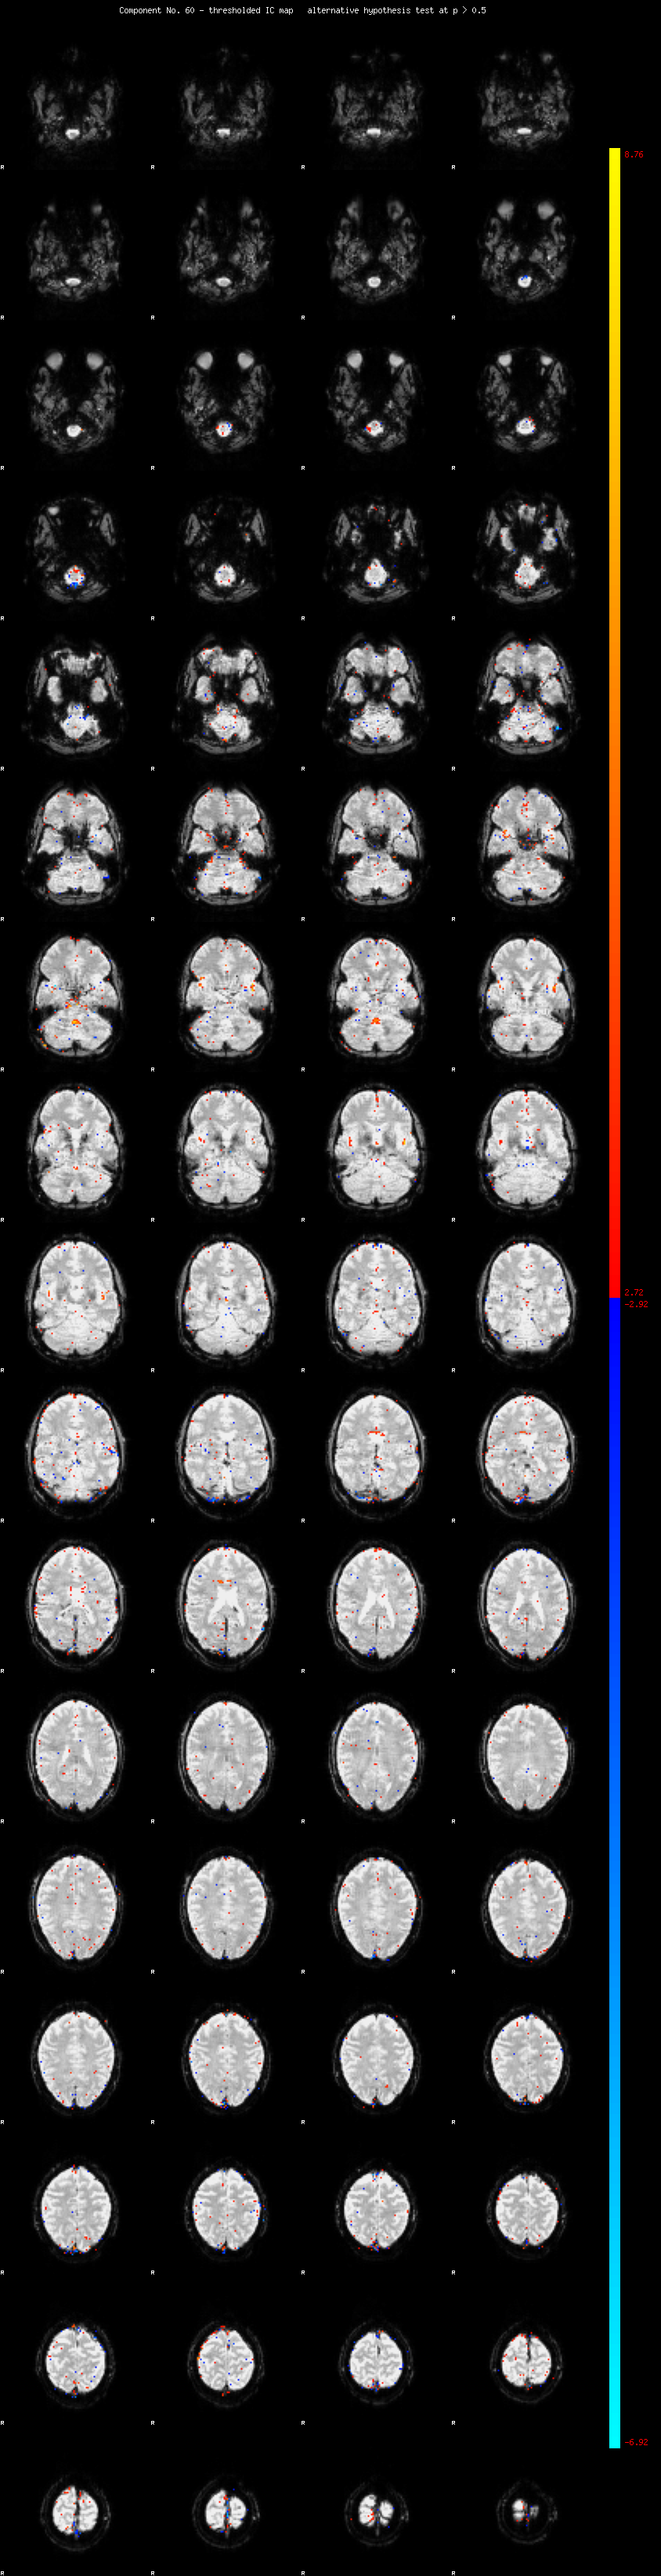

MELODIC Component 60

0.86 % of explained variance;     0.57 % of total variance

MMfit